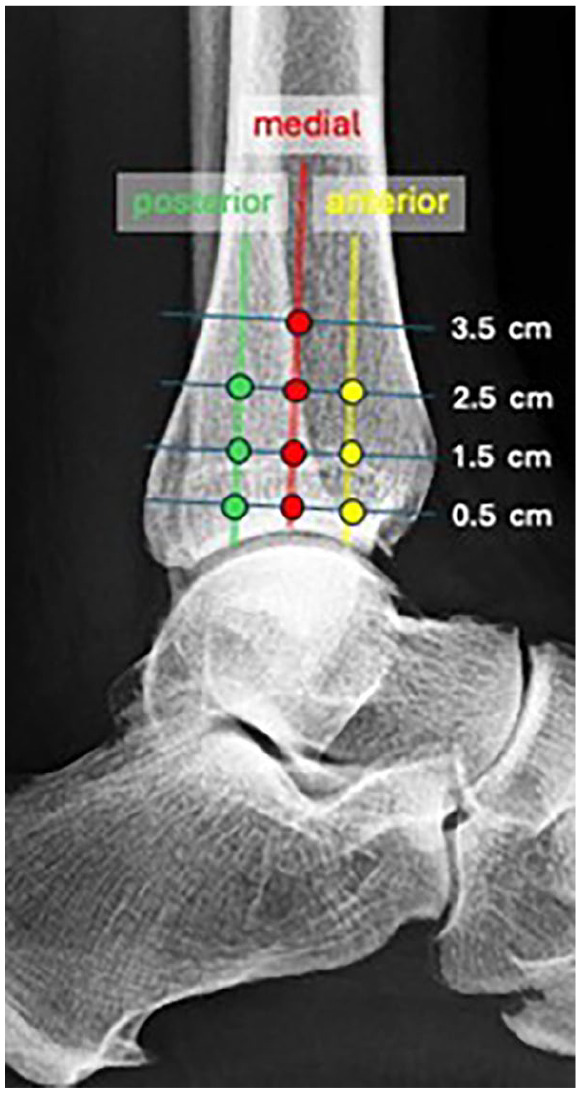

Methods: Biomechanical fixation stability with suture button device (TightRope; Arthrex, Naples, FL) placed at 4 distances from the tibiotalar joint line (0.5, 1.5, 2.5, and 3.5 cm) and 3 trajectories (anterior, medial, and posterior) were studied using cadaveric lower extremities with created syndesmotic injuries. Nondestructive testing was conducted on a biaxial servo-hydraulic load frame. The load application consisted of 2 portions: (1) axial compression simulating weightbearing and (2) external rotation of the ankle (up to 12 degrees and under 7.5 Nm) around the long axis of the tibia combined with weightbearing. Fibular motion and syndesmotic widening were tracked using motion analysis to quantify stability.

Results: Fixation placed at 0.5 or 1.5 cm from the joint line in medial or posterior trajectories resulted in the lowest increases in fibular rotation under loading. More proximal or anterior placements led to increased fibular motion and decreased rotational stability. Ankle width changes were minimal in most groups, although slightly increased widening occurred at proximal and anterior placements.

Conclusion: Placement of the syndesmotic suture button fixation 0.5-1.5 cm of the joint line in medial or posterior orientations provides the most rotationally stable fixation in a cadaveric model. These findings support flexibility in syndesmotic suture button fixation positioning when hardware constraints limit ideal placement.